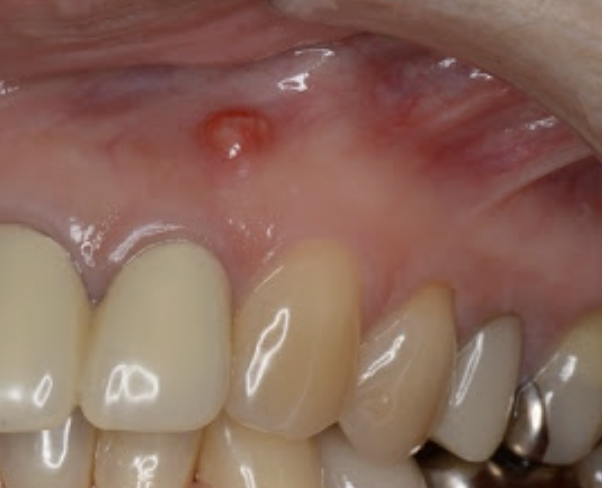

症状: 歯の根の先端の骨が溶けたり、歯茎に膿が溜まったり腫れたり(フィステルと呼ばれる小さなニキビのようなもの)します。痛みがない場合もありますが、感染は進行しています。

専門用語: **根尖性歯周炎(こんせんせいししゅうえん)**と呼ばれます。